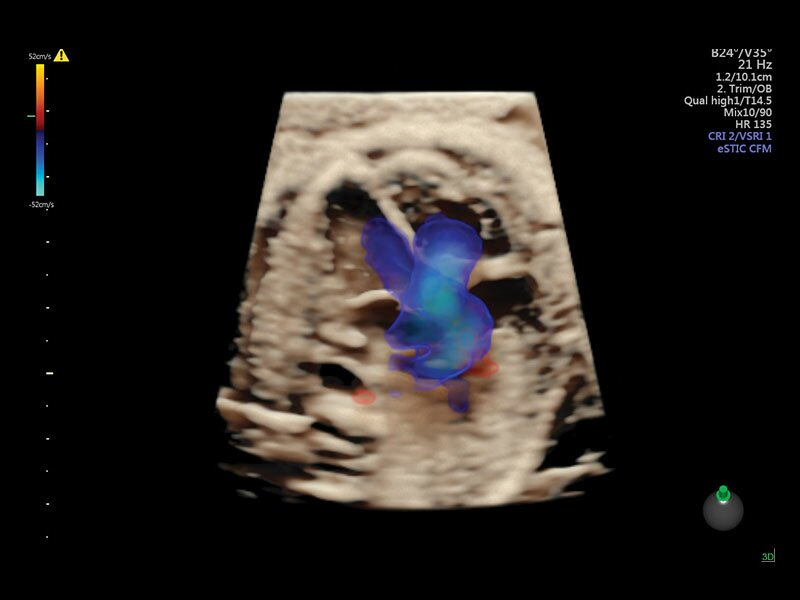

Клинические изображения

• Высокочувствительный допплер (HD-Flow)

• Реалистичный объёмный кровоток в режиме ЦДК (Radiantflow)

• HDlive Flow - перемещаемый источник света, совместимый с визуализацией кровотока в 3D

• HDlive Flow Silhouette - режим "Силуэт" с выделением границ полостей сердца и сосудов, совместимый с визуализацией кровотока

• Электронный STIC - eSTIC

• Advanced STIC - расширенный программный пакет для исследования сердца плода в режиме 4D для механических и электронных объемных датчиков:

• Использование цветного, энергетического допплера, В Flow - режим STIC.

• Сочетание с М-режимом - STIC-M-Mode

• Перемещаемый источник света - STICflow

• SonoVCADHeart - программное обеспечение для исследования сердца плода в режиме 3D/4D (быстрый доступ к плоскостям сканирования) по рекомендациям ISUOG

Объемное сканирование Voluson — 3D/4D вашей мечты

Объемное УЗИ на Voluson E10 — это не просто потрясающе красивая картинка, это ценный инструмент получения дополнительной информации при обследовании женщин.

Voluson E10 поддерживает инновационные технологии формирования изображений — HDlive Silhouette и HDlive Flow, которые позволяют увидеть мельчайшие детали. Алгоритм SonoRenderlive упрощает рабочий процесс и дает возможность реконструировать изображение поверхностей, определяя область перехода между тканью и жидкостью.

• Технология HDlive Flow — повышает реалистичность визуализации сосудистых структур, улучшая восприятие глубины (по сравнению с традиционным цветовым допплером и функцией HD-Flow).